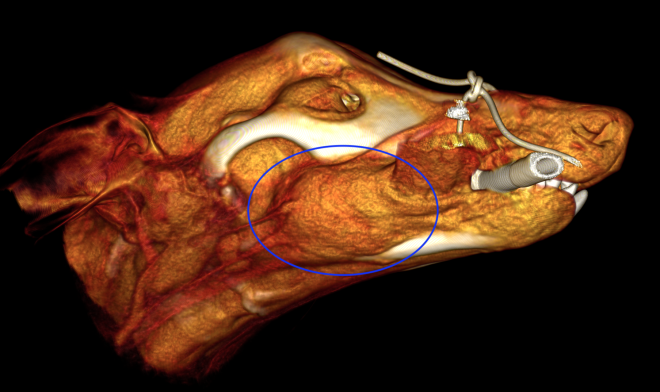

今回治療させていただいたワンちゃんは、口の奥に出来物が見つかったとのことで来院され、頬粘膜〜下顎の歯肉腫瘤を生検したところ、メラノーマと診断されました。

腫瘍の増殖スピードが速く、日に日に大きくなっていき、このままでは食べられなくなる可能性がありました。

手術は、腫瘍に片側下顎骨の大部分をつけて切除しました。また、下顎リンパ節、内側咽頭後リンパ節も切除しました。病理検査では、腫瘍は取り切れており、リンパ節転移もなしとの結果でした。